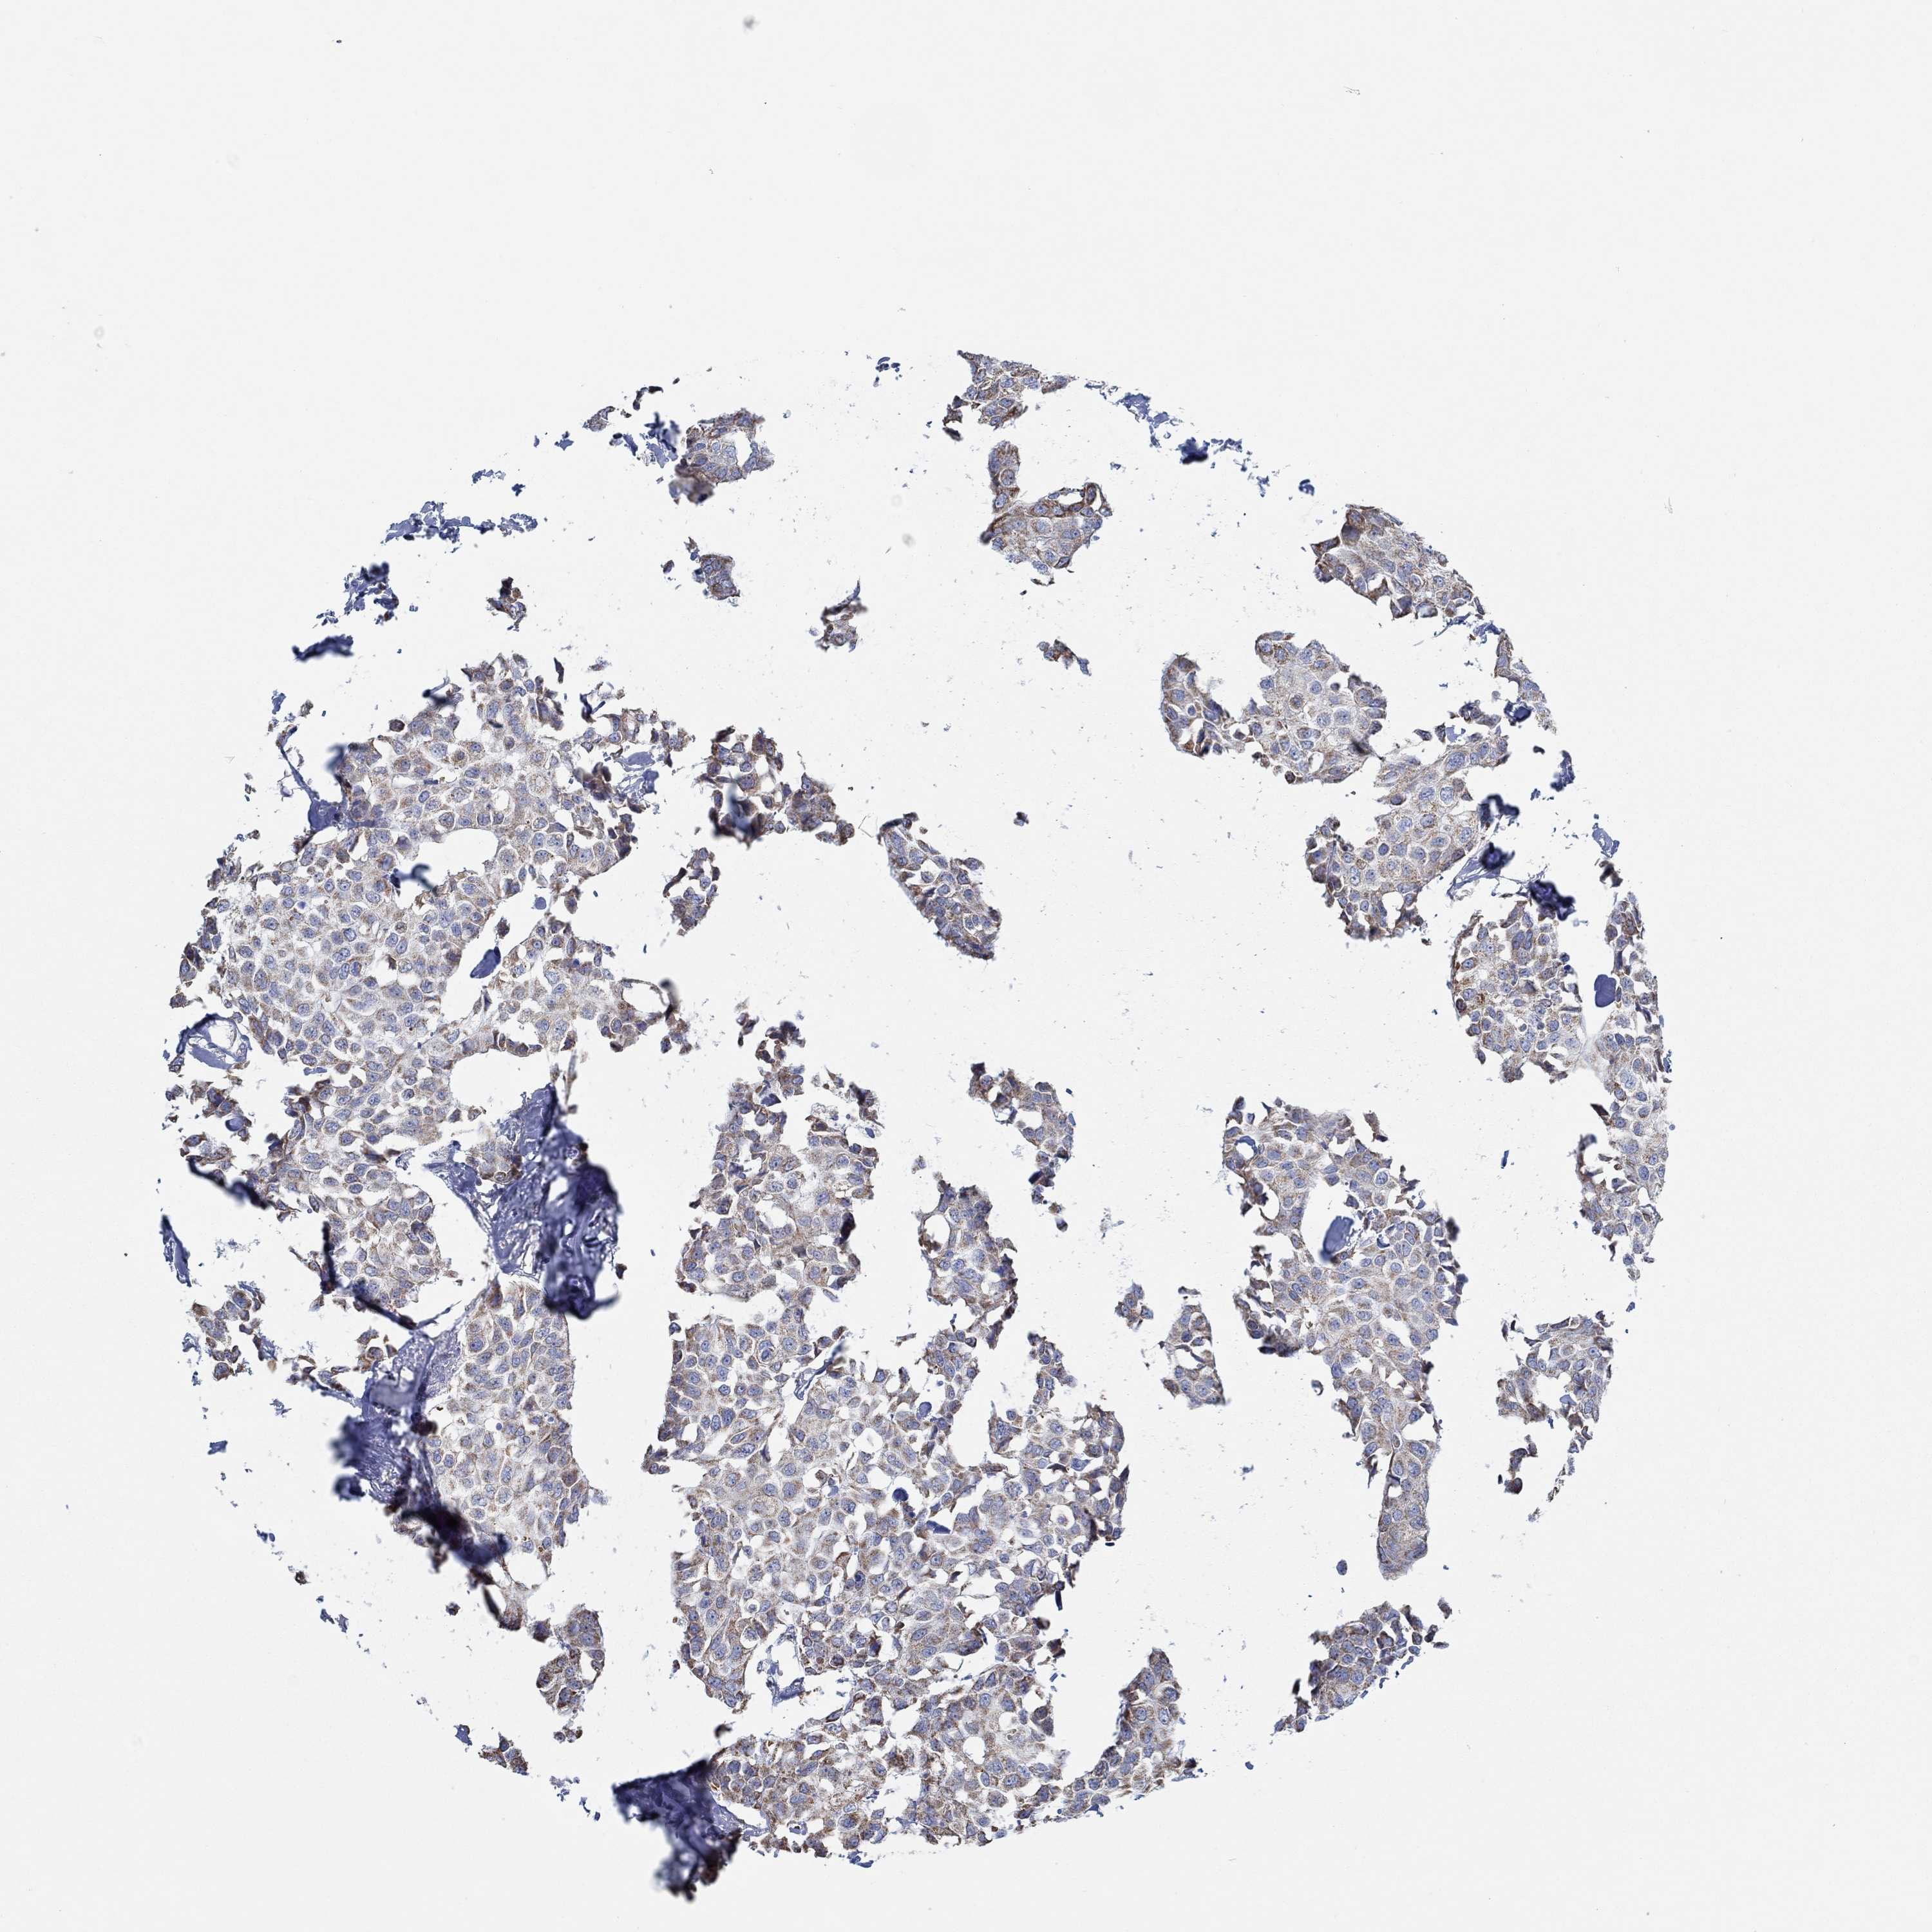

CANCER BREAST CANCER Show tissue menu

BRCA TCGA BRCA VALIDATION PROTEIN EXPRESSION